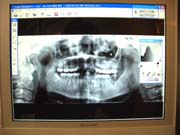

【デジタルレントゲン】

当院では、被曝量が大幅に軽減されているデジタルレントゲンを導入しております。

現像までの待ち時間も短く、診察台のパソコン画面にて鮮明なレントゲン写真をご覧頂けます。

又、現像の際に廃液も出ないため、環境にも優しいものです。